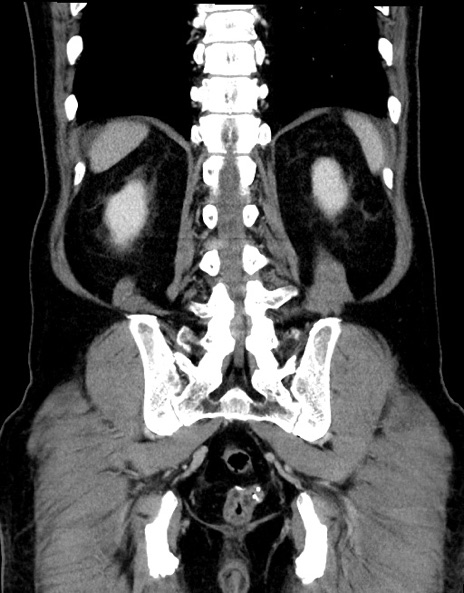

症例15(冠状断像)

【症例】70歳代男性

【主訴】腹痛

【現病歴】今朝から腹痛あり。全体的に痛い。特に左上の方。排ガスが今日はない。冷や汗が出る。

【既往歴】直腸癌術後

【身体所見】左側腹部〜上腹部に圧痛あり。腹膜刺激症状明らかなではない。軽度反跳痛。左下腹部に術後瘢痕あり。

【データ】WBC 7700、CRP 0.02

横断像